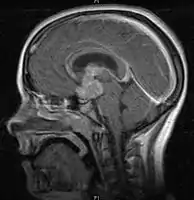

- Mainly located in midline structures, suprasellar region or pineal gland, also basal ganglia and hypothalamus

- Suprasellar Germinoma